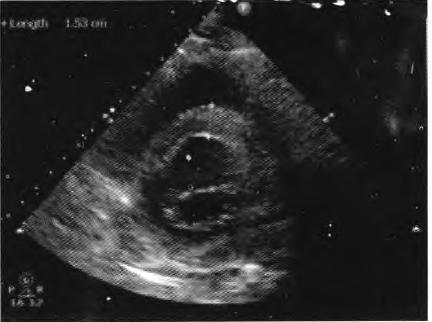

患者择期于10月25日行冠状动脉介入治疗,术前常规给予地塞米松10 mg静脉注射,右侧桡动脉穿刺成功后,经鞘管送多功能造影导管至主动脉窦部,对比剂选择碘帕醇(商品名:碘必乐),导管“吾烟”后数秒钟,患者血压骤然降低至50/30 mmHg,心率逐步增快至90次/min左右,予羟乙基淀粉130/0.4氯化钠注射液(万汶)加压快速静脉滴注100 mL,反复3次静脉注射多巴胺3 mg,血压65/40 mmHg左右,约3 min后心率降至40次/min左右,监护示室性逸搏心律,继之心跳、呼吸骤停。持续胸外按压,气管插管机械通气,持续静脉泵入肾上腺素0.2仙g/(kg•min),并间断4次静脉注射肾上腺素0.5 mg,血压维持在105/50 mmHg左右,进一步行左室造影,见图1。以及左冠状动脉造影,见图2。氧饱和度降至75%,考虑对比剂致高敏反应,引起过敏性休克,静脉滴注甲泼尼龙500mg,经右侧股动脉路径行主动脉内球囊反搏术(intra.aortic balloon pump,IABP)治疗,同时联系外科、麻醉科、体外循环科经左侧股动脉一股静脉行体外膜肺氧合(extra—corporeal membrane oxygenation,EC—MO)支持治疗。ECMO置人后将患者由导管室转送至冠心病监护病房(coronary care unit,CCU)继续抢救治疗,床边心脏超声,见图3。提示室间隔水肿(厚度1.53 cm)。在置人ECMO初期维持绝对镇静,下调直至停用血管活*药性**物,心律以室性逸搏心律为主(持续约48 h),偶然有室速、室颤发作,未作处理。在置人ECMO第3天因急性肾衰竭行床旁连续静脉静脉血液滤过(continuous veno—venous hemofiltration,CVVH)治疗,第4天后患者心率、血压稳定,复查心脏超声提示左心室射血分数40%,撤除ECMO,此后依次拔除气管插管、撤除IABP以及停止CVVH等治疗,患者恢复良好,于11月14日出院。

图3心脏超声提示室间隔水肿,厚度1.53 cm

在冠状动脉介入诊疗术中发生心脏骤停,对于尚处于心肌梗死(尤其是急性ST段抬高型心肌梗死)急性期的病例,要首先考虑心肌梗死后机械并发症(如心室游离壁破裂、室间隔穿孔等)、冠脉急性血栓栓塞事件以及医源性冠脉损伤等,并迅速行相关检查措施排查,如能排除以上危重情况,则要考虑对比剂导致过敏性休克。该患者术中左室造影排除心室游离壁破裂,左冠状动脉造影排除左主干或左冠血管急性血栓栓塞事件以及医源性冠脉损伤,再结合患者存在药物(多种抗生素)过敏史,因此,诊断对比剂致过敏性休克明确。后期心脏超声提示“心肌水肿”,亦是器官组织对过敏的一种表现。